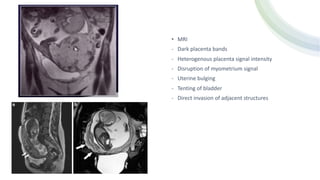

• MRI

- Dark placenta bands

- Heterogenous placenta signal intensity

- Disruption of myometrium signal

- Uterine bulging

- Tenting of bladder

- Direct invasion of adjacent structures